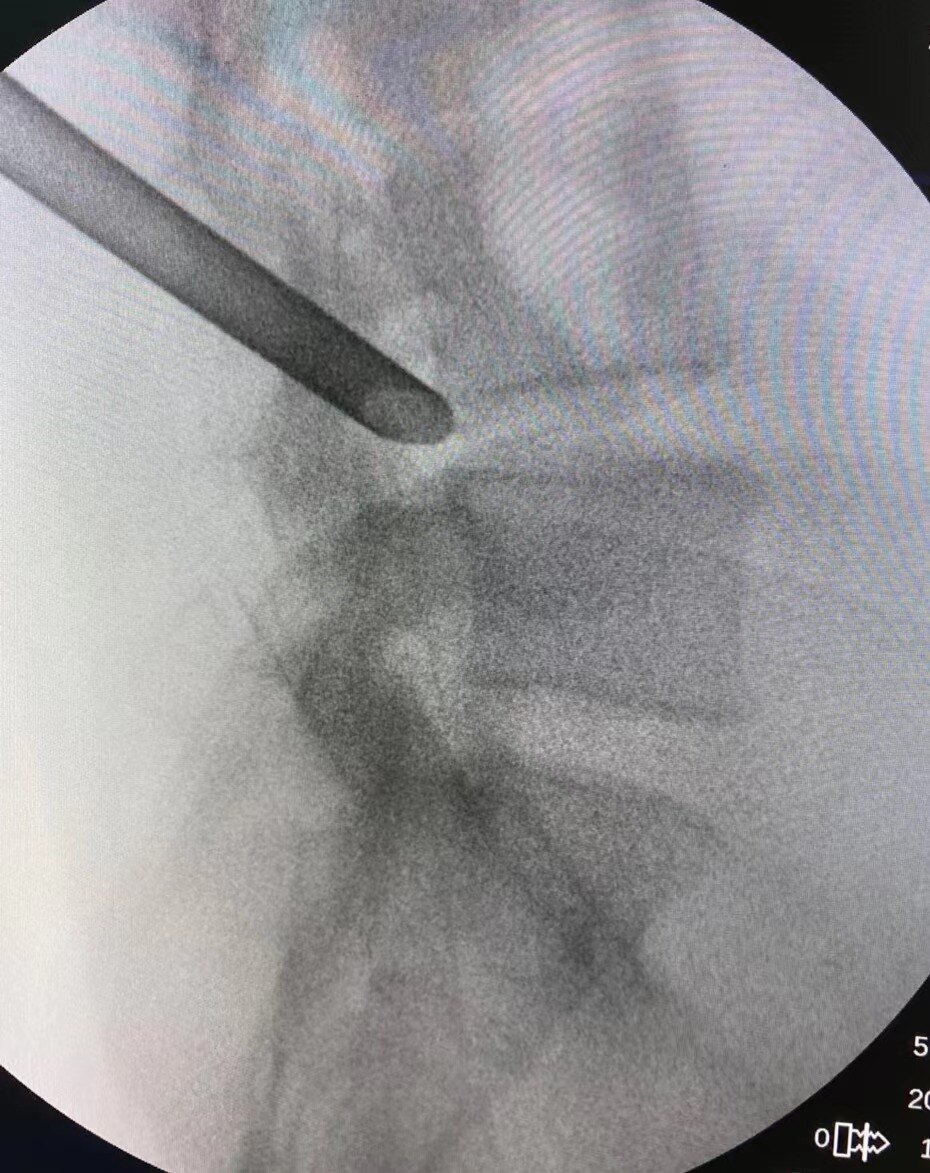

另一类是显微镜椎间盘摘除、内镜下椎间盘摘除、经皮椎间孔镜下椎间盘摘除等微创外科技术使手术损伤减小,取得了良好的效果。

目前椎间孔镜技术发展十分成熟,大部分腰椎间盘突出症(包括巨大的、脱出型、游离型腰椎间盘突出症)、合并椎间盘钙化及黄韧带钙化的腰椎间盘突出症、部分腰椎管狭窄症和开放术后复发的腰椎间盘突出、I度稳定性腰椎滑脱合并腰椎间盘突出都可以进行椎间孔镜手术。